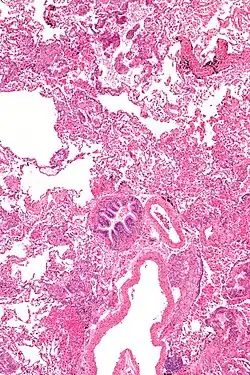

Limfangioleiomiomatoza, LAM, naczyniakowatość limfatyczna (łac. i ang. lymphangioleiomyomatosis) – rzadka choroba śródmiąższowa płuc, polegająca na niekontrolowanym rozplemie nietypowych komórek (komórki LAM) wokół oskrzeli, naczyń chłonnych i krwionośnych.

Z czasem tworzą się złożone z komórek LAM torbiele i zgrupowania komórek, przerastają tkanki w płucach. Niszczą one prawidłową tkankę płucną, zastępując ją torbielami. Doprowadza to po pewnym czasie do niewydolności oddychania.